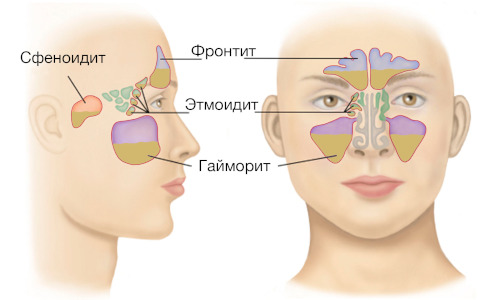

FRONTIT

There are two main forms of frontal sinusitis - acute and chronic. In the acute phase of frontal sinusitis, the mucous membrane of the frontal sinuses thickens significantly, and swelling appears inside. They put pressure on the blood vessels and this ...

NOSE FRACTURE

Severe traumatic effects can not only damage the bones of the nose, but also lead to damage to the anatomical structures surrounding it - the sinuses and frontal processes. Injuries affecting the ethmoid bone are especially dangerous, since due to damage ...

NASAL RINSING

Indications Rinning the sinuses is an effective method of treating and preventing infectious diseases. Doctors prescribe this procedure in the following cases: For prolonged runny nose, when symptoms persist for more than two weeks Inflammation of the ...